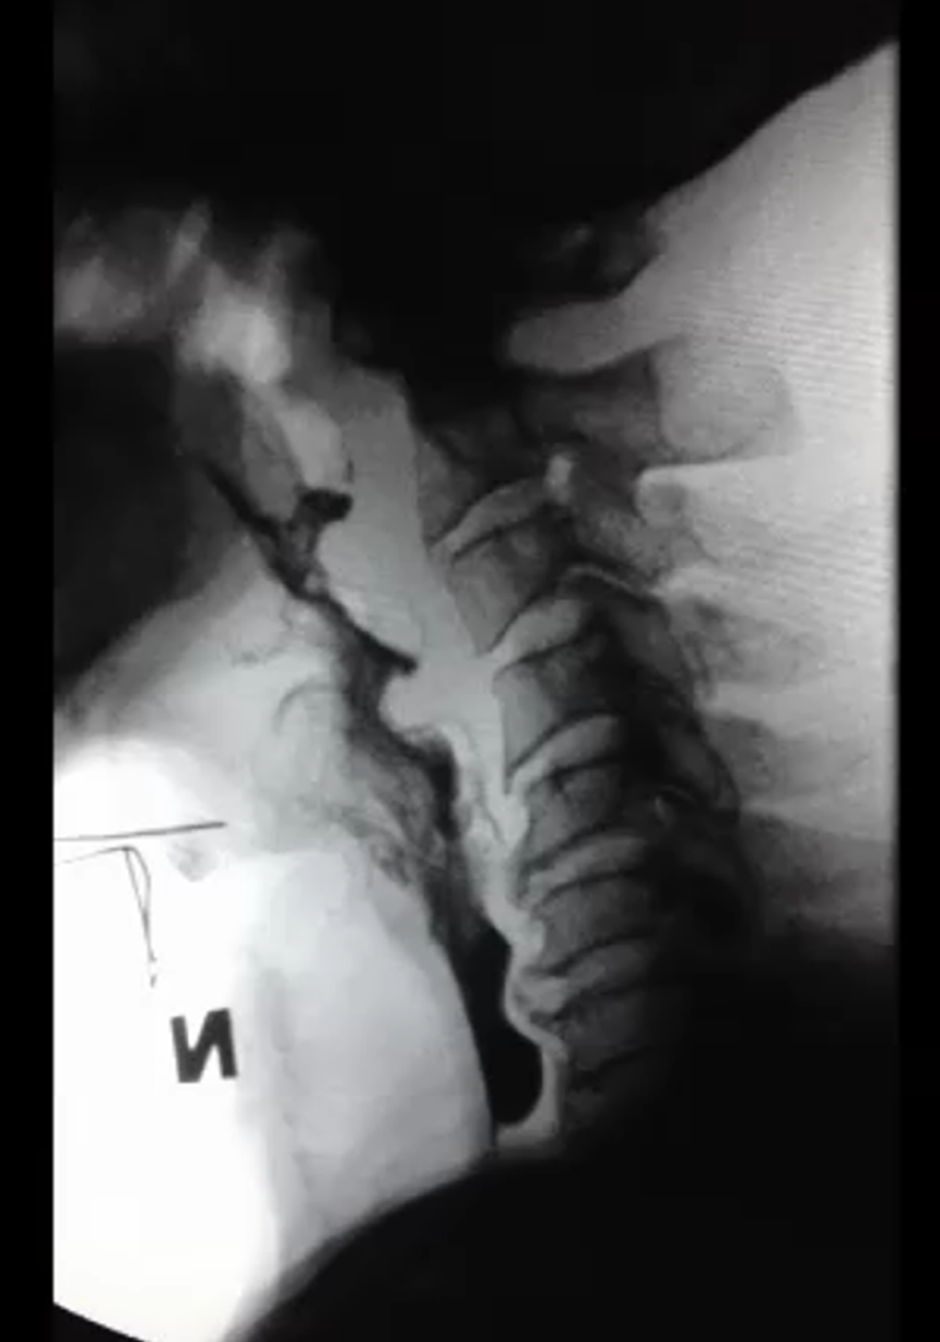

The following are some of the slides from the VFS workshop:

VFS: AnatomyVFS: The normal swallowing sequenceVFS: Case Study on the “Tennis Player” A chronic severe dysphagia client was successfully treated with therapy using sEMG biofeedback. This client managed to resume a regular diet and thin fluids and had his PEG tube removed.